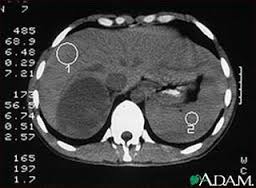

پردازش تصویر شامل چندین مرحله می باشد که مهمترین آنها بخش بندی است. بخش بندی فرآیندی است که ورودی را به اجزای سازنده اش تقسیم میکند.

در این پایاننامه، برای حل مسئلهی تقطیع تصویر، تصویر ورودی بعد از پیش پردازشهای اولیه به گراف تبدیل میشود.

هدف از این عمل، جداسازی اجزاء اصلی تشکیل دهنده تصویر است. بطوری که آنها را جهت اندازهگیریهای بعدی آماده نماید. Segmentation یکی از پردازشهای نسبتاً مشکل میباشد. کیفیت نتایج زیربخشها بستگی به کیفیت مراحل segmentation دارد.

در این روش ابتدا تصویر مورد نظر سیاه و سفید می شود، سپس سایز این تصویر کوچکتر شده، تصویر باینری و گراف آن ایجاد و اختلاف شدت روشنایی پیکسلها بر اساس همسایگی ۴-گانه محاسبه شده و این گراف توسط الگوریتمهای MAX-K-CAT و فرا ابتکاری جستجوی ممنوع افراز می گردد. خروجی همان تصویر ورودی است که به دو بخش پس زمینه (ریه) و شی (ضایعه) تقسیم شده است.

به منظور بررسی کیفیت جواب های حاصله، از تصاویر سی تی اسکن ریه استفاده شد. نتایج آماری نشان داد که بیش از ۹۰ درصد از موارد، الگوریتم پیشنهادی به جواب های مناسبتری دست یافته است.